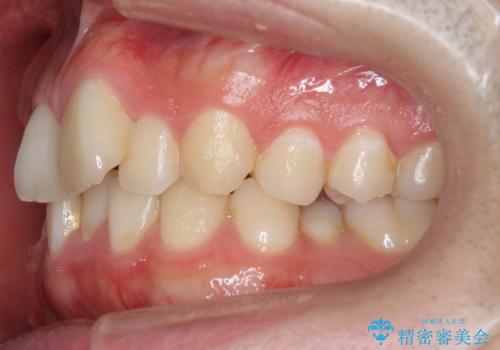

- 前歯のがたつきを主訴に来院。

左下の奥歯を後ろに移動して、中に入ってすれちがっていた小臼歯を並べました。

奥歯を後ろに移動させるために、矯正用のミニスクリューを用いました。(インプラント矯正)